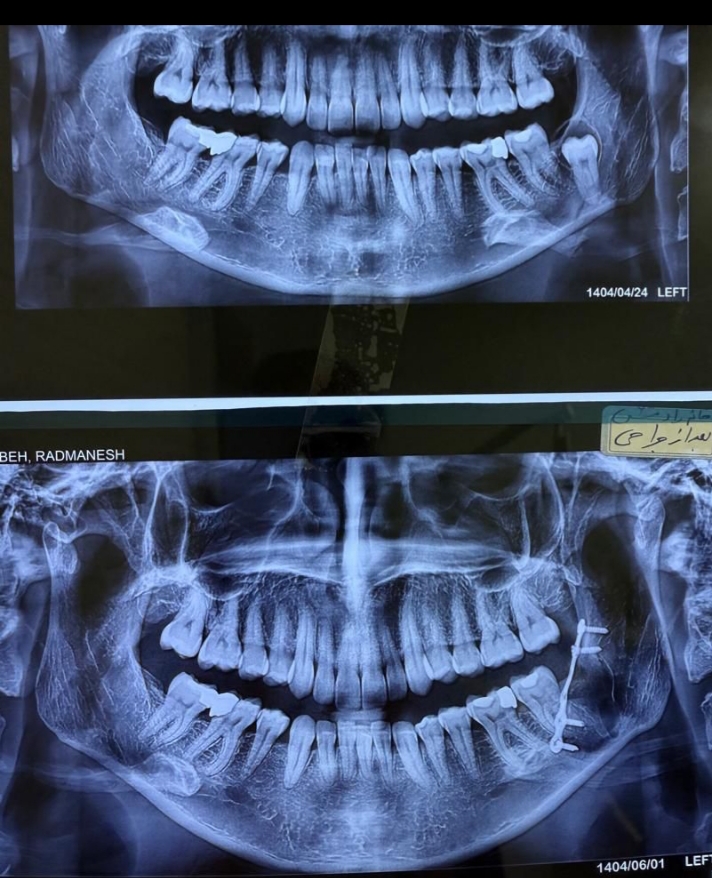

شکستگی متعدد صورت

بازسازی شکستگی صورت